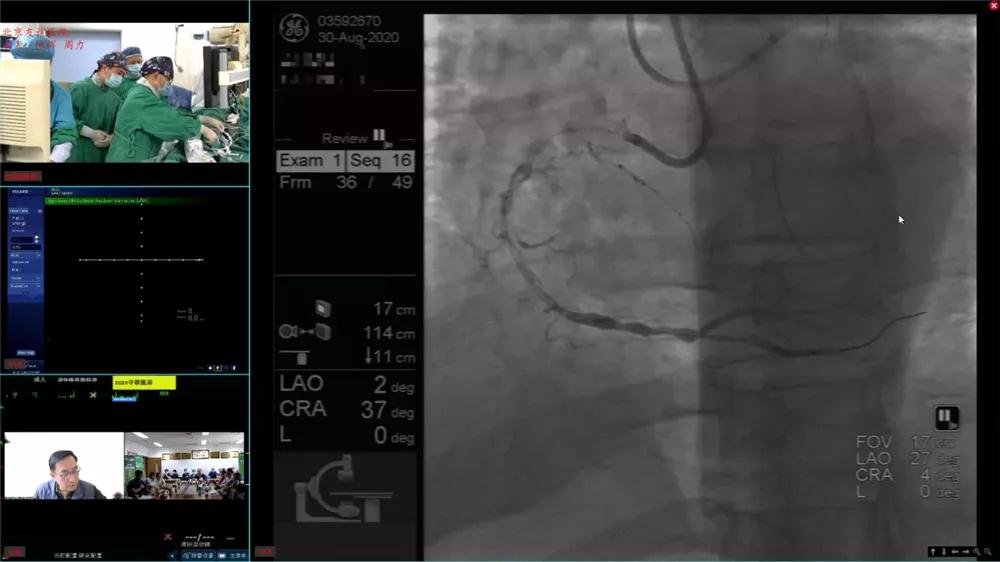

作为友谊冠脉介入新技术新进展学习班(BFCI)的一个重要环节,8月30日,心脏中心冠脉介入团队在陈晖教授领导下,成功完成四例高难度冠脉慢性完全闭塞病变手术,并进行现场直播,吸引了众多同行上线学习与观摩。慢性完全闭塞病变作为冠脉介入手术的“最后壁垒“,是衡量冠脉介入团队水平的一把标尺。此次四台高难度手术介入适应证明确,术前评估充分,分别由陈晖教授、李东宝教授、赵慧强教授和姚道阔教授主刀,两台采用正向开通,两台采用逆向技术开通,个个精彩纷呈,示教性极强,术后无一例并发症出现。本次直播还邀请了阜外医院吴永健教授、窦克非教授、安贞医院柳景华教授等国内十余位顶尖介入专家现场讨论交流,分享手术经验,给年青术者提供了一次难得的学习机会,为此次为期三天的BFCI大会画上了圆满的句号。